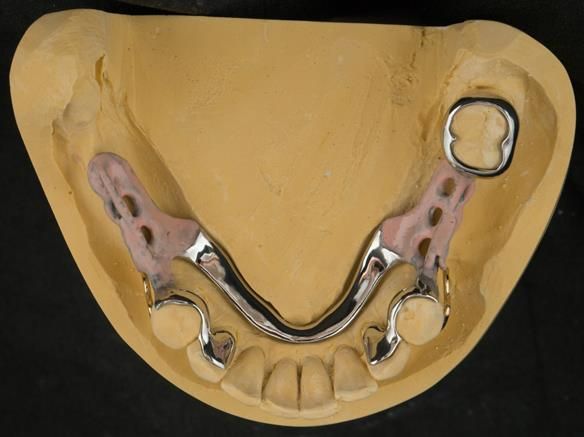

This newsletter describes in step by step detail Angela's transition through immediate partial dentures to crown supported definitive metal based dentures.

- Partial denture with new crowns (this is what the patient wanted - owing to the increased risk of implant failure due to type 1 diabetes)

The clinical situation and treatment process is shown in detail below with photographs. I (Finlay Sutton) provided the clinical work and Rowan Garstang provided the technical work.